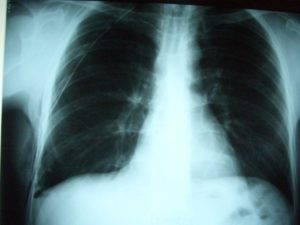

Для обнаружения легочных заболеваний в первую очередь используется флюорография. Эту процедуру необходимо проводить ежегодно, в основном она направлена на выявление ранней стадии туберкулеза. Однако опытный рентгенолог может выявить на снимке образовавшиеся плевральные спайки, которые выглядят тенями. Причем форма их не меняется в зависимости от вдоха и выдоха.

При необходимости дополнительно назначается рентген. Как правило, спайки располагаются в нижней части легкого. При этом будет более темная картинка, а также может быть частичная деформация грудной клетки и диафрагмы.

Диагностика и лечение

Определить наличие спаек в легких можно при помощи флюорографии. Этот метод исследования является наиболее достоверным. Дополнительно могут назначить рентген легких. Врач определяет наличие спаек по характерным темным пятнам, которые видны при получении рентгеновского снимка. Изменения могут также наблюдаться в диафрагме — она становится менее подвижной.

Самым распространенным методом диагностики легких является – флюорография. Но если врач подозревает, что у пациента есть спайки, то больной отправляется на рентген. По рентгеновскому снимку распознать синехию можно по мутным темным пятнам. Она выглядит, как теневое затемнение и неподвижна при вдохе и выдохе.

Иногда выявляется деформация грудной клетки и диафрагмы. Чаще всего спаечный процесс отмечается в нижней части легкого. Такой вид спаек – плевродиафрагмальный, а вид спаек в верхней части – плевроапикальный.